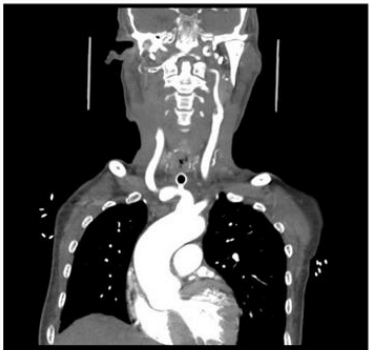

Fig 3

Imaging Findings

Emergency multiphasic CT carotid angiography using IV contrast was performed, including axial thin cuts with multiplanar and maximum intensity projection (MIP) reformatted images.

The study revealed:

• Abnormal fistulous communication between the brachiocephalic artery and the upper anterior tracheal wall, approximately 3 cm below the cricoid cartilage.

• The fistula measured approximately 5 mm in length.

• Dense secretions were noted in the trachea and main bronchi.

• Diffuse marked atherosclerotic changes were observed in the visualized portion of the thoracic aorta, characterized by mural irregularities, thickening, and intimal calcifications.

• Mild atherosclerotic changes were noted in the bilateral common carotid arteries and the extracranial segments of the internal carotid arteries, with no evidence of significant stenosis.

Figure 3